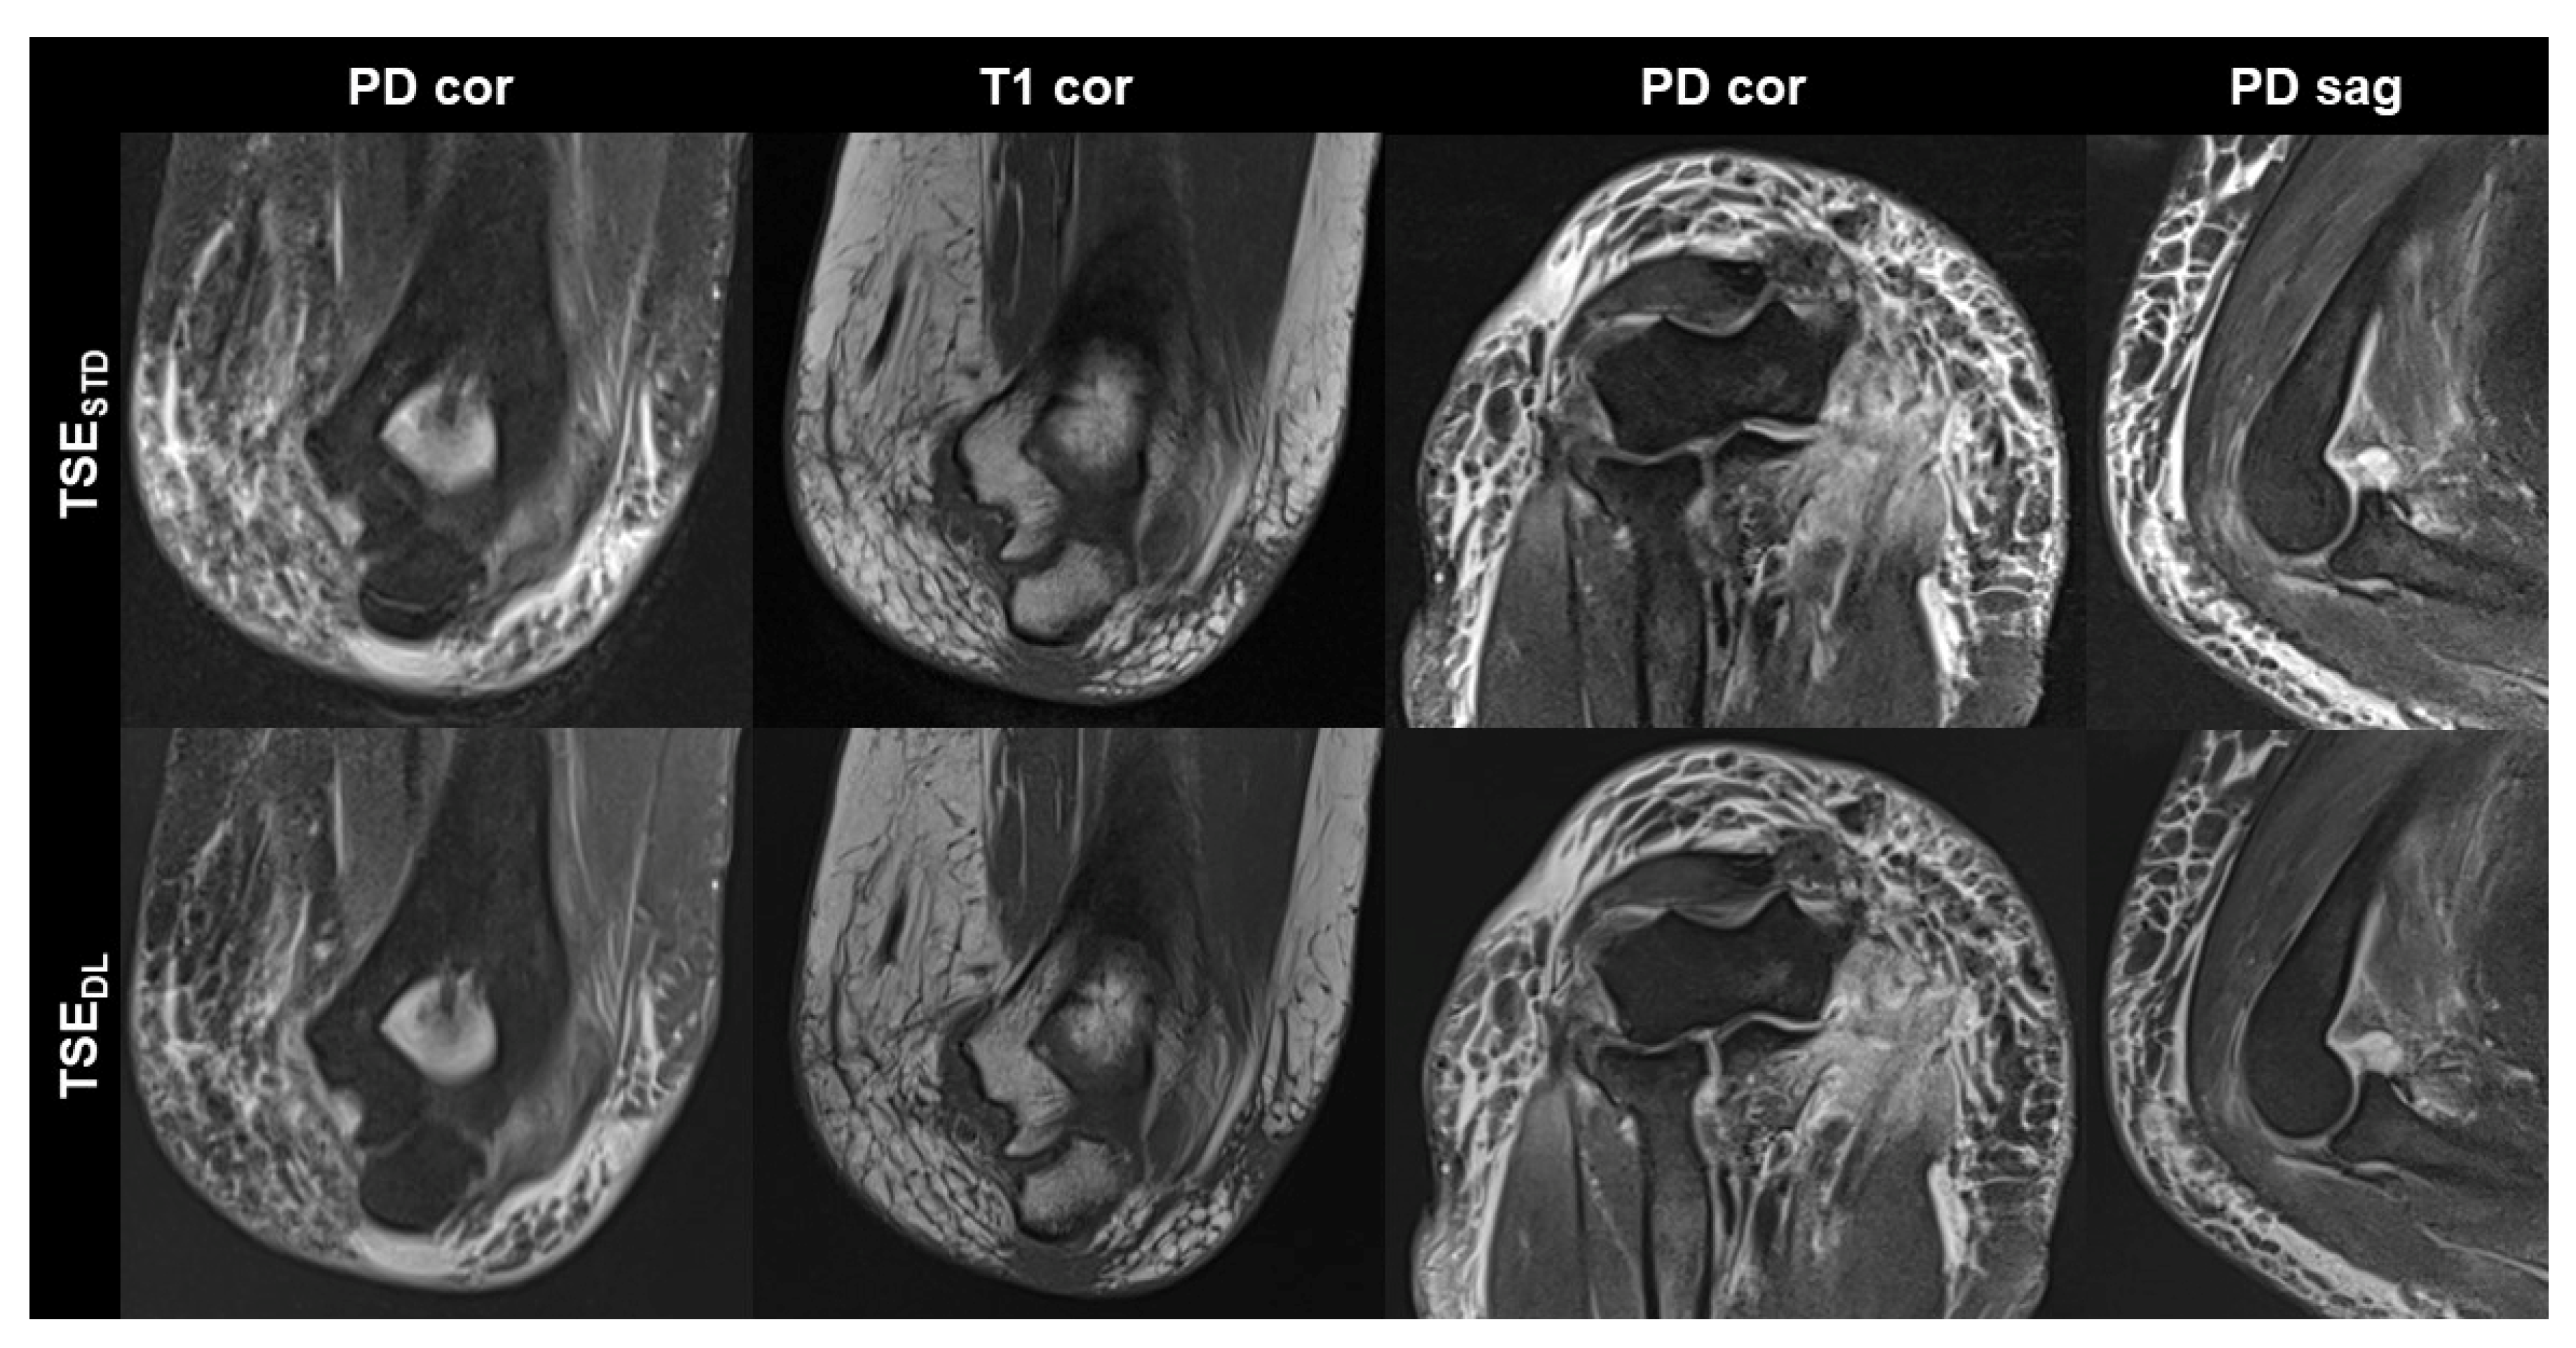

TSEDL was successfully performed in each of the 17 included participants (mean age 43 ± 16 (20–70), years, eight men). Seven exams were performed at 1.5 T and 10 exams at 3 T. TSEDL enabled a scan time reduction by more than 35% at 1.5 T (TSEDL 8:19 min vs. TSESTD 13:06 min) and by more than 55% at 3 T (TSEDL 6:48 min vs. TSESTD 15:15 min). Image examples with comparisons of TSESTD and TSEDL are displayed in Figure 1, Figure 2, Figure 3 and Figure 4.

Figure 1. Non-contrast elbow MRI acquired at 1.5 T in a 51-year-old female patient with the institution’s standard turbo spin echo (TSE) sequences (TSESTD, upper row) and deep learning-reconstructed TSE sequences (TSEDL, lower row). Increased edge sharpness in the TSEDL images is primarily seen in the coronal and sagittal T1-weighted sequences (T1 cor and T1 sag). In the fat-saturated coronal and axial PD-weighted images (PD cor and PD ax) the DL reconstruction shows decreased noise.